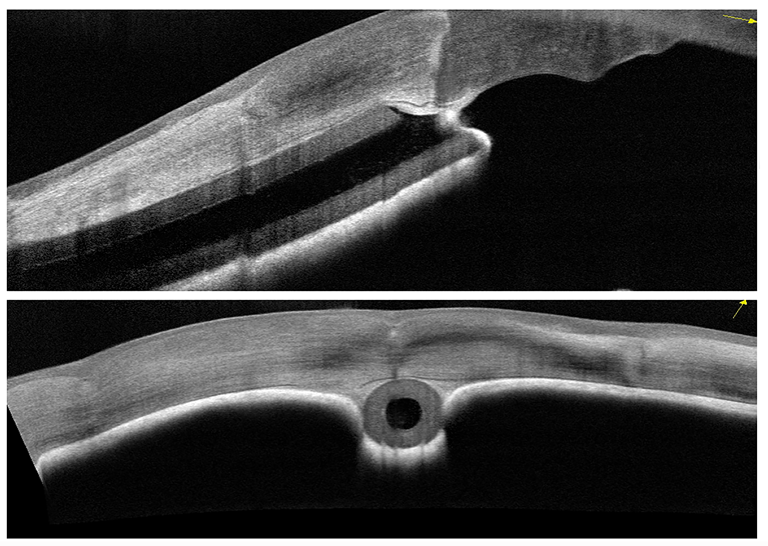

Glaucoma Shunt Tube

Presented by Sean Grout, OCT-CThis photograph received 1st Place in the category "Optical Coherence Tomography" and was displayed at the 2024 ASCRS/OPS Society Exhibit.